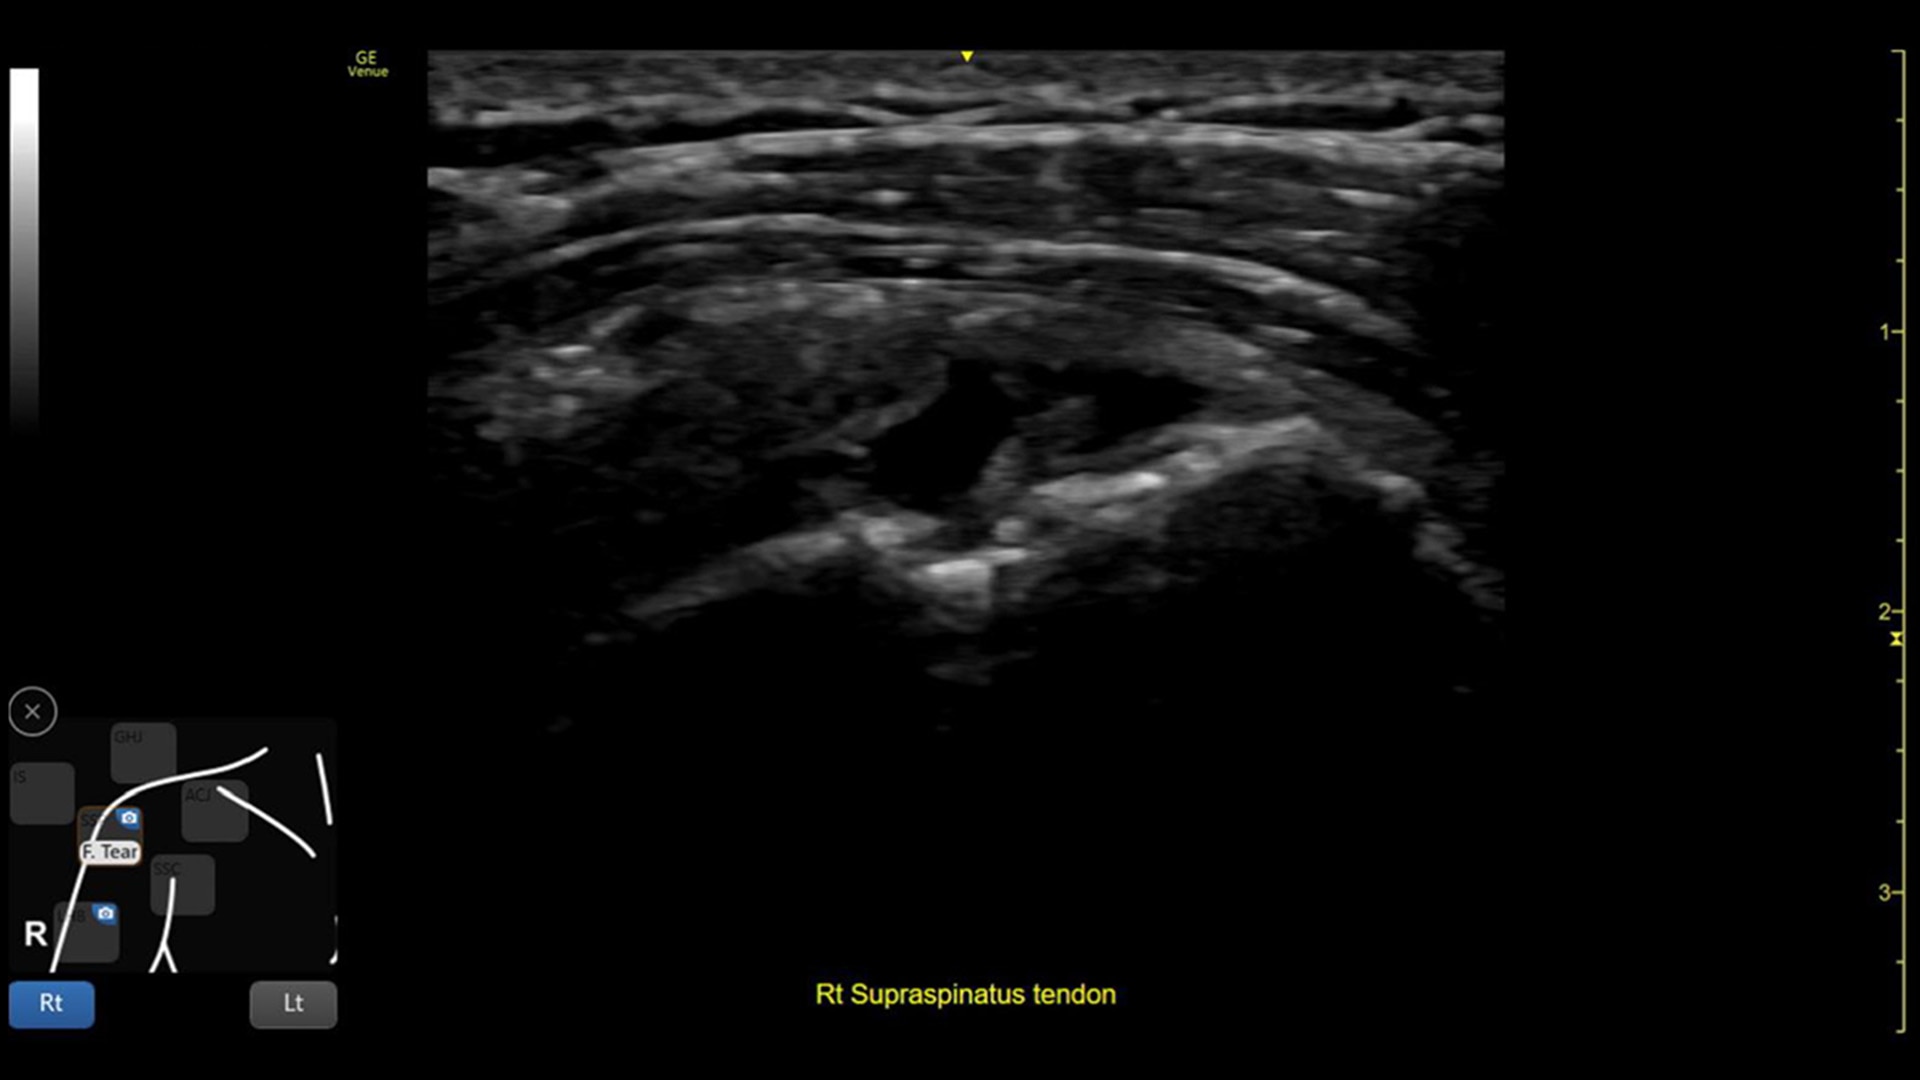

Point of care ultrasound for musculoskeletal

Providing musculoskeletal (MSK) practitioners with effortless and precise ultrasound, the Venue family of AI-enabled point of care ultrasound systems allows you to quickly assess tendons, muscles, and joints, and manage patient progress during a course of treatment. Improving both the patient and practitioner experience, Venue family products enable fast assessments and accurate needle procedures.

VENUE COACH MSK

Simplifying MSK scans

This easy-to-use exam documentation tool assists users through exams by providing reference images and anatomy markups. Multiple anatomical areas and helpful video tutorials help clinicians to acquire the scans they need.

Focus areas include:

• Shoulder

• Knee

• Hip

• Elbow

• Wrist/Hand

• Ankle/Foot

• MSK Diagrams: Simplifies documentation and assists the clinician in follow up for patients. No need to manually type findings—you can simply assign a label from a pre-populated list that correlates with the images. Get a single view diagram with one click image storing, keep track of assessments and show trends in response to therapy.

• Reference Image: Reference image provides anatomy mark-ups to assist novice users in scanning the correct anatomy

• Bilateral mode: Helps you to view the opposite side of the same zone for comparison (available for Shoulder preset)